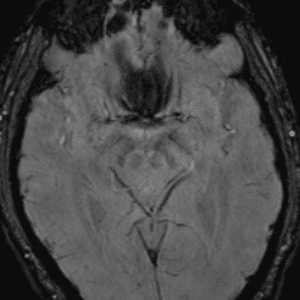

Neurodegenerative Diseases